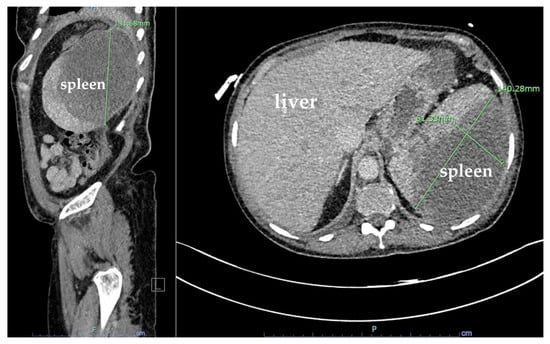

Computed tomography (CT) of the abdomen and pelvis revealed hepatomegaly of 23 cm with no other acute findings (Figure 2). During hospitalization, hemoglobin dropped to 6.1 g/dL, requiring transfusion of a unit of packed RBC, which improved hemoglobin to 7.0 g/dL. The nausea and vomiting persisted, warranting a repeat CT of the abdomen and pelvis, which showed new development of hemoperitoneum in the left abdomen surrounding the spleen, leading to concerns about subcapsular hematoma and an enlarged spleen by 13.2 cm (Figure 3). Additionally, the patient developed dyspnea, and chest X-ray revealed a pleural effusion in the left lung base.

Figure 2. Coronal plane computed tomography (CT) scan with IV contrast of the abdomen and pelvis showing hepatomegaly (23 cm). Spleen was normal.

Figure 3. Coronal and sagittal plane computed tomography (CT) scans with IV contrast of the abdomen and pelvis showing hemoperitoneum (white arrows) and mild splenomegaly (13.2 cm).